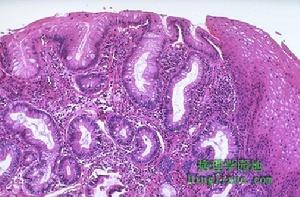

繼發性化膿性腹膜炎在腹膜炎的初期,腹膜受細菌侵犯或消化液刺激後,一方面動員機體的防禦功能,對細菌及其毒素開始進行拮抗,大量漿液性滲出液能稀釋腹腔內毒素,其中吞噬細胞、中性粒細胞及補體能產生殺菌作用,同時滲出液中的纖維蛋白沉積後與周圍器官和網膜粘連從而阻止感染的擴散;另一方面,胃腸道穿孔流出的胃液、膽汁、實質臟器破裂的血液和壞死的臟器組織對細菌感染起到輔助作用。隨著炎症反應不斷加劇,大量中性粒細胞死亡,組織壞死,細菌和纖維蛋白凝固,滲出液逐漸由清變濁或為膿性。膿液的特性和細菌的種類有關,大腸埃希桿菌及厭氧脆弱類桿菌等混合感染,膿液多呈黃綠色,稠厚;若具有糞樣特殊臭味,為厭氧菌感染的特徵。